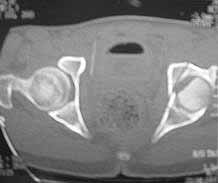

Male 22 yrs of age, RTA, front seat passenger in a truck. Sustained grade IIIB fracture of Tibia, and a Posterior dislocation of the Ipsilateral Left Hip.

Emergent closed reduction performed, and Tibial wound debrided. Next day Exfix applied and fibula plated. Initially femoral head fracture was not appreciated and it was thought that this is a posterior wall fracture. Presently two weeks down the line, Tibial wound is better but not completely healthy. and plastics want to wait for another five days, before they flap it. I enclose radiographs, Judet view, Ct scans in this and following mails.

2)The femoral head fracture involves the anter-inferior part and not the weight bearing superior dome. Also while moving the hip after taking weight off the traction, it does seem pretty stable. Should it be fixed even then?

I'd remove the displaced and malrotated head fragment, clean it on the back table, apply 2 or 3 glide holes, then clean the hip joint of debris, look at the acetabular fracture thru the joint and assure that it hasn't further displaced.

Based on the selected images that you shared with us, I would not leave it as is. The fragment is significant in terms of its size and location and displacement.